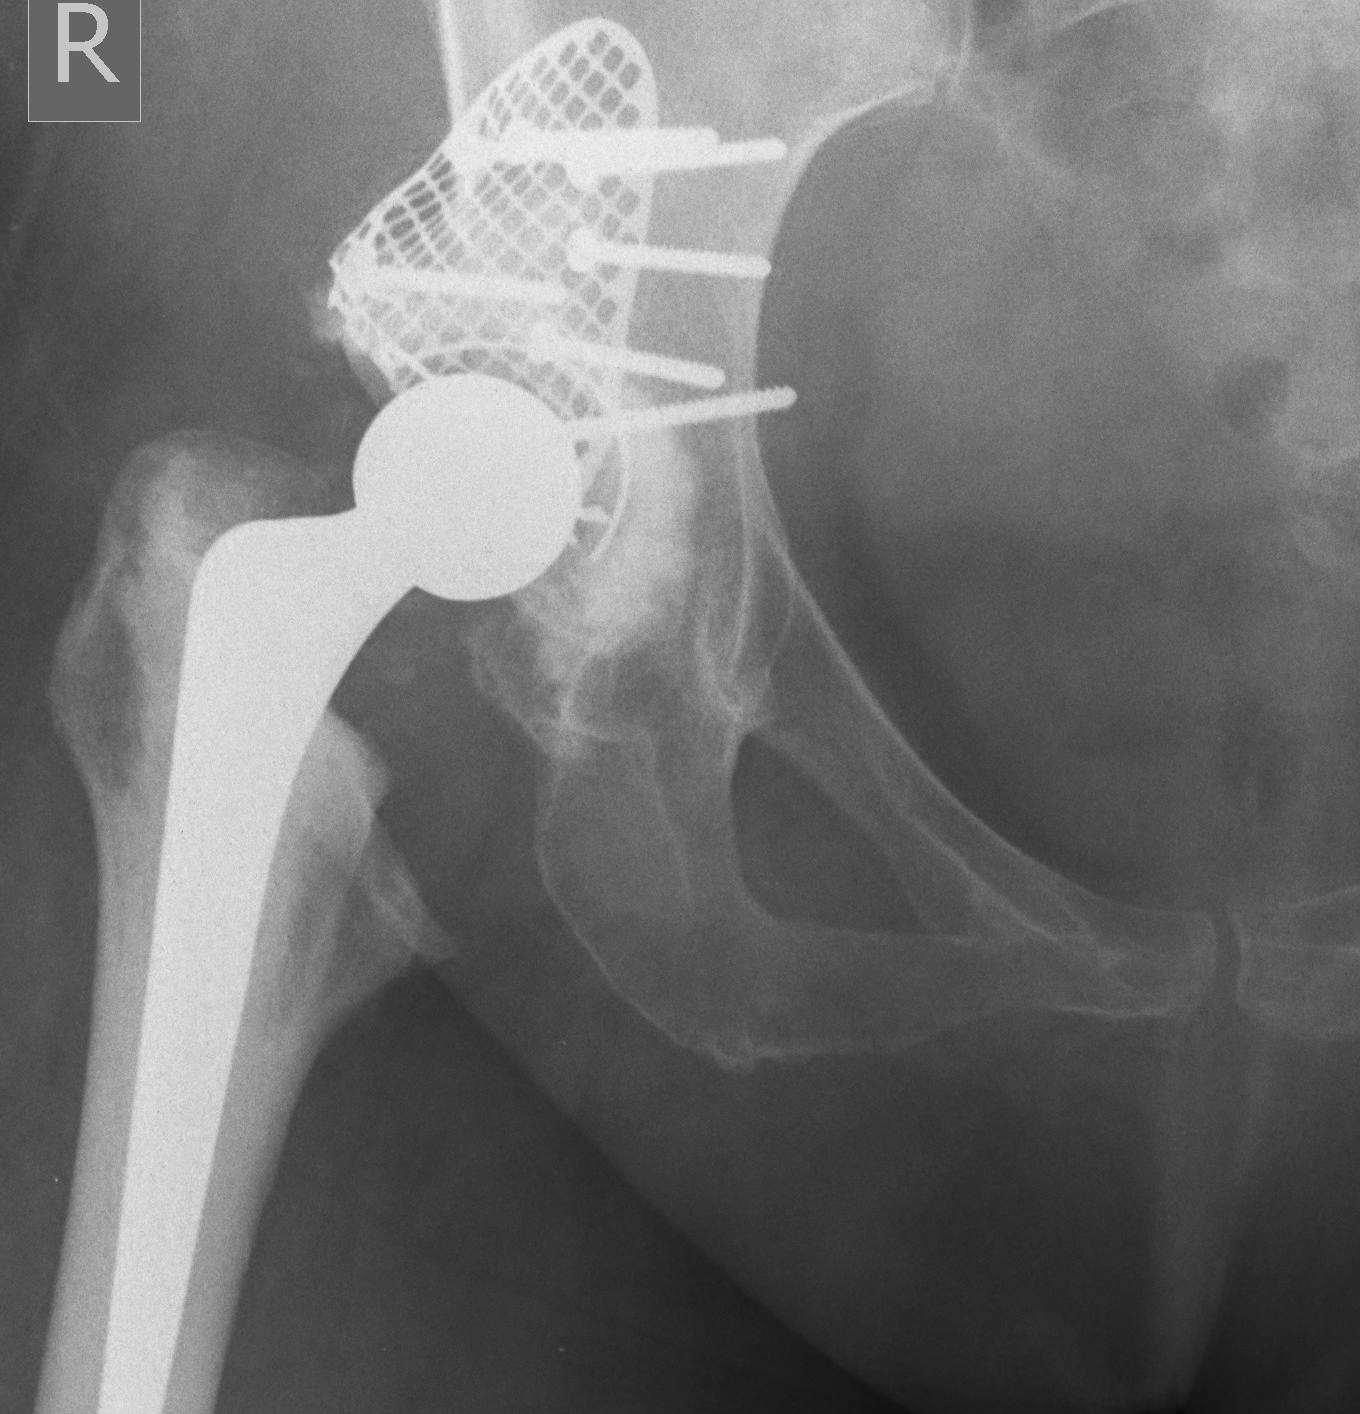

Trabecular metal cup with augments / 3D printed cups

Zimmer trabecular metal acetabular revision system

Acetabulum Reconstruction

- tantalum cup with augments